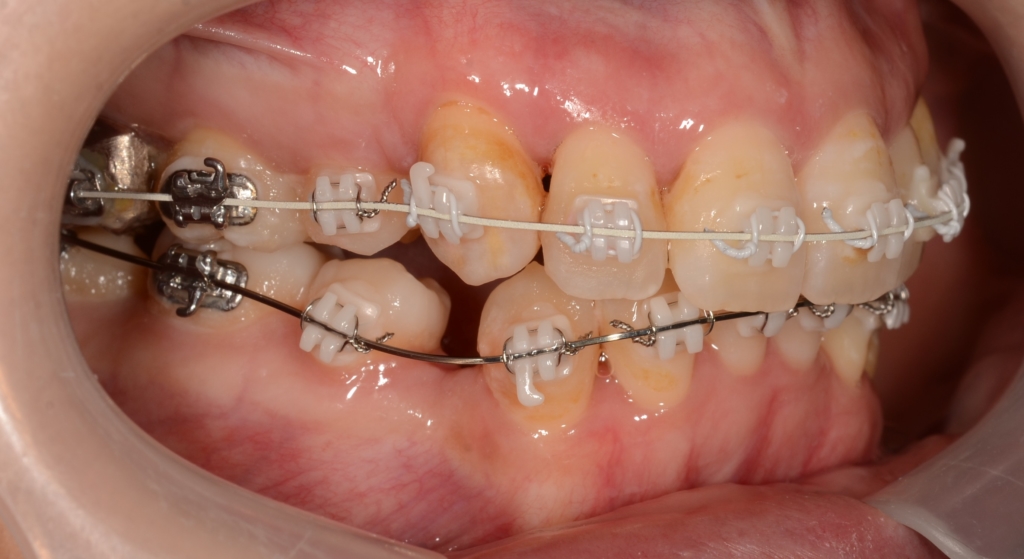

【6か月経過】

上下とも前歯はきれいに並びましたが、左右とも(特に左側)上顎前突(出っ歯)の噛み合わせが残っています

【噛み合わせを良くするために】

上下とも前歯はきれいに並びましたので、次のステップに移ります。

噛み合わせとしては上顎前突(出っ歯)が残っています。 (特に左側)